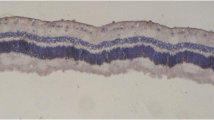

Enucleated eyes were fixed in 10 % formalin and embedded in paraffin. Paraffin-embedded specimens were cut into 4-µm-thick sections as horizontal section through the optic disk of the eye and mounted on slides. The sections were stained with hematoxylin and eosin for the evaluation of disruption of inner retina (from the inner plexiform layer to the inner limiting membrane), epiretinal membrane formation, the presence of retinal fold, and abnormal blood vessel growth.

Layers of the retina were observed as intact in sham group using H–E staining methods (Fig. 1). Proliferative changes such as the formation of new blood vessel or preretinal membrane was not observed in this group. However, sections from PVR groups showed markedly edematous inner retina and new blood vessel formation along with retina inner surface. Some of the vessels were filled with blood cells and dilated. Furthermore, epiretinal membrane was also recognized. An epiretinal membrane was a fibrocellular tissue found on the inner surface of the retina (Fig. 2a, b). This membrane tightly adhering to the internal limiting membrane in some areas, in addition to the retina, was convoluted in some places. While the mean PVR stages of the without drug group was found 2.28 ± 0.75, a PVR + drug group was 1.42 ± 0.53. The difference between the PVR group and PVR + drug groups was statistically significant (p = 0.04) (Table 3). On the other hand, although retinal damage was recognized as alleviated in PVR + drug group, the lesions did not completely improve. Degenerative alterations like focal edematous alterations, epiretinal membrane formation, and localized vascular changes were still present in this group (Fig. 3a, b). In addition, a significant difference was observed in both groups (PVR group and PVR + drug) in terms of the score of PVR when compared with the sham group (p = 0.001 and p = 0.04, respectively). Inflammatory cells were not observed in any of PVR groups.